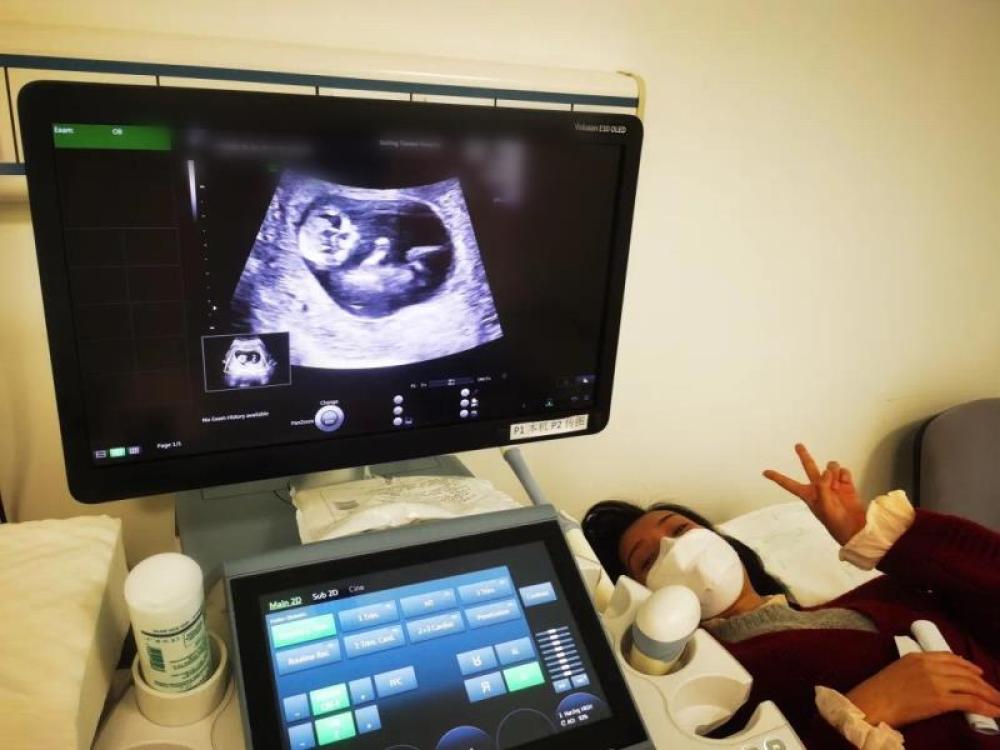

今天一早,妻子去醫(yī)院進行B超檢查,同事用手機拍攝下了B超顯示屏上的畫面,記錄下了這個87天的小家伙第一次“亮相”。

圖為北京天壇醫(yī)院袁磊愛人做B超檢查。

“袁磊,看看你們家寶寶,可愛嗎?”收到同事發(fā)來的視頻,第一眼就看哭了,身邊的同事看完視頻也哭了。

視頻里,這個小家伙好像聽到了外面的召喚,在媽媽的肚子里伸手、踢腿、翻身,用各種動作進行回應(yīng)……看到他那小胳膊小腿,一種從未有過的幸福感不停地向上涌,眼淚怎么也控制不住。

其實在武漢這么多天,他一直就是我的牽掛,今天終于看到他了,那種感受真是又緊張又激動,雖然還看不清他的樣子,但是已經(jīng)感受到他的活力。